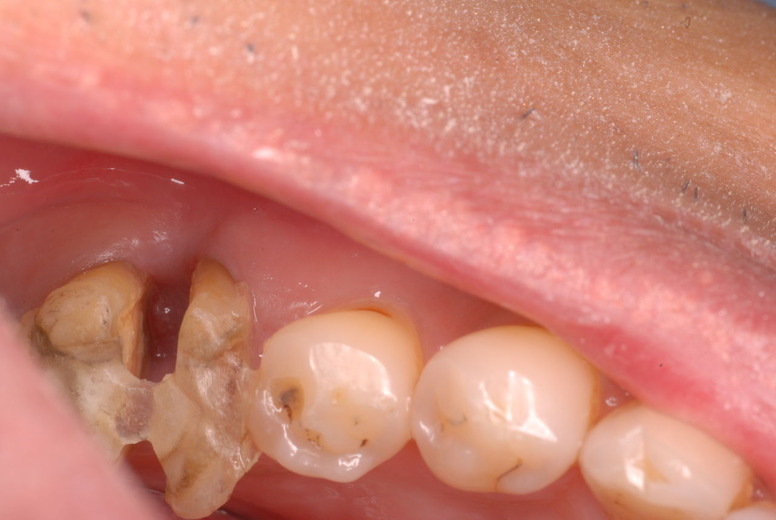

親知らずを取ることを嫌がる方が多いのですが、もし親知らずとその隣の14歳大臼歯の間に虫歯ができたり歯周病を罹患した場合、どれほど治療が大変で再発も起こりやすいか理解できない方がおおいのです。

写真左下の親知らずが痛くなり抜歯しました。その後歯茎を除去して虫歯を露出させる処置を二回ほどしています。

レントゲンでは小さいですが、こう言う虫歯が一番怖いのです。

治療の成功率は極めて悪くすぐ再発しやすいのです。